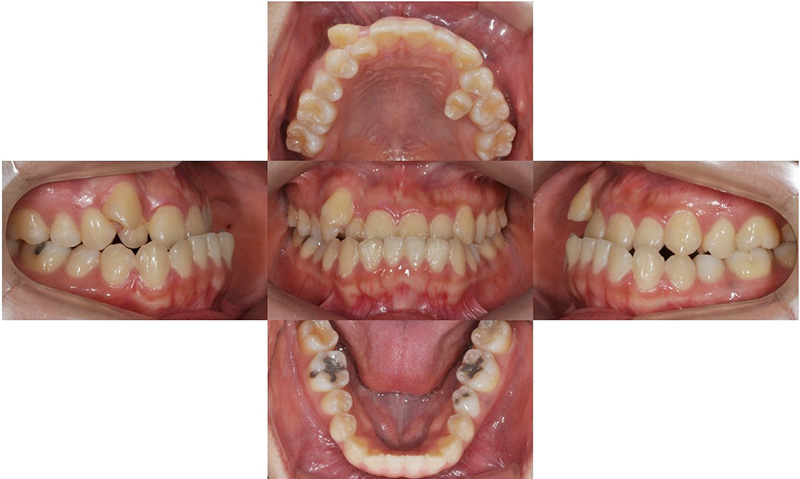

2017.12

본 환자는 오른쪽 송곳니가 나올 공간이 부족하여 드라큘라 이빨처럼 높게 맹출하였고(high canine), 왼쪽 두번째 작은 어금니는 아예 맹출할 공간이 부족하여 입천장으로 맹출해 있는 것을 볼 수 있습니다. 삐뚤빼뚤한 위턱 치아들에 비하여 아래 치아는 가지런한 편이었고, 어금니의 교합관계는 양호한 편이었습니다.